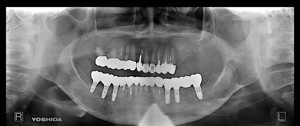

`ƒCƒ“ƒvƒ‰ƒ“ƒgŽèp‚ðŽÀۂɑ̌±‚³‚ê‚½Š³ŽÒ—l`

ƒCƒ“ƒvƒ‰ƒ“ƒgŽ¡—ªpŒã‚P”NˆÈã—ÇD‚ÉŒo‰ß‚µAˆÀ’肵‚½ó‹µ‚ƂȂèA

‚Rƒ–ŒŽ–ˆ‚̃ƒCƒ“ƒeƒiƒ“ƒXŽ¡—Êú‚É“ü‚ç‚ê‚½Š³ŽÒ—l‚ÉA

“–ˆã‰@‚̃Aƒ“ƒP[ƒg‚É‚¨“š‚¦‚¢‚½‚¾‚¢‚Ä‚¨‚è‚Ü‚·B